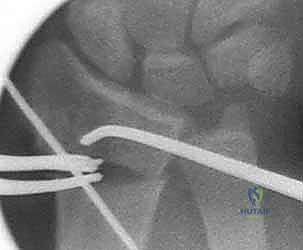

3. قص العظم التصحيحي (The Osteotomy)

بناءً على التخطيط الثلاثي الأبعاد المسبق، يستخدم الدكتور هطيف مناشير عظمية دقيقة جداً لعمل شق في العظم في نقطة التشوه الأصلية. يتم فتح العظم وتعديل زاويته واستعادة طوله الطبيعي.

4. الترقيع العظمي (Bone Grafting)

عندما يتم تعديل زاوية العظم وفتحه، يتكون فراغ عظمي. لضمان التئام سريع وقوي، يقوم الدكتور هطيف بملء هذا الفراغ بطعم عظمي (Bone Graft). يمكن أخذ هذا الطعم من عظم الحوض الخاص بالمريض، أو استخدام بدائل العظم الصناعية عالية الجودة.